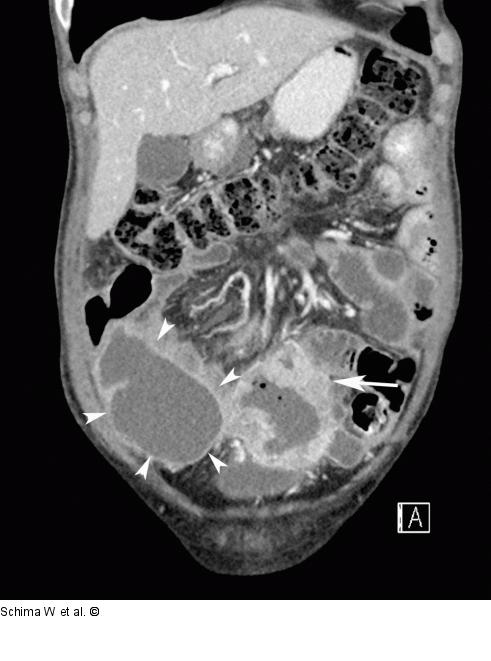

Abbildung 2b: MDCT - 3D Die koronale 3D-Rekonstruktion der MDCT zeigt anschaulich, dass der Tumor offenbar von einer Dünndarmschlinge ausgeht (Pfeil). Im rechten Unterbauch angrenzend an den Tumor findet sich eine große Abszess-suspekte Retention (Pfeilspitzen). |

Die koronale 3D-Rekonstruktion der MDCT zeigt anschaulich, dass der Tumor offenbar von einer Dünndarmschlinge ausgeht (Pfeil). Im rechten Unterbauch angrenzend an den Tumor findet sich eine große Abszess-suspekte Retention (Pfeilspitzen). |